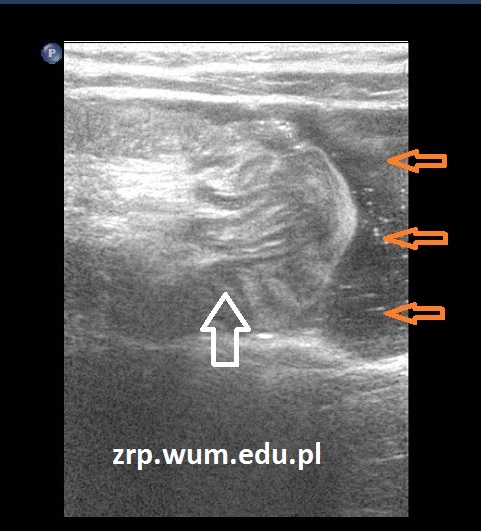

Pacjentka została przyjęta do Szpitala, wykonano nieskuteczną próbę odgłobienia wlewem wodnym pod kontrolą USG (biała strzałka - wgłobienie, pomarańczowe strzałki - płyn w jelicie grubym). Pacjentka operowana - stwierdzono wgłobienie patologiczne, z uchyłkiem Meckela jako punktem prowadzącym.